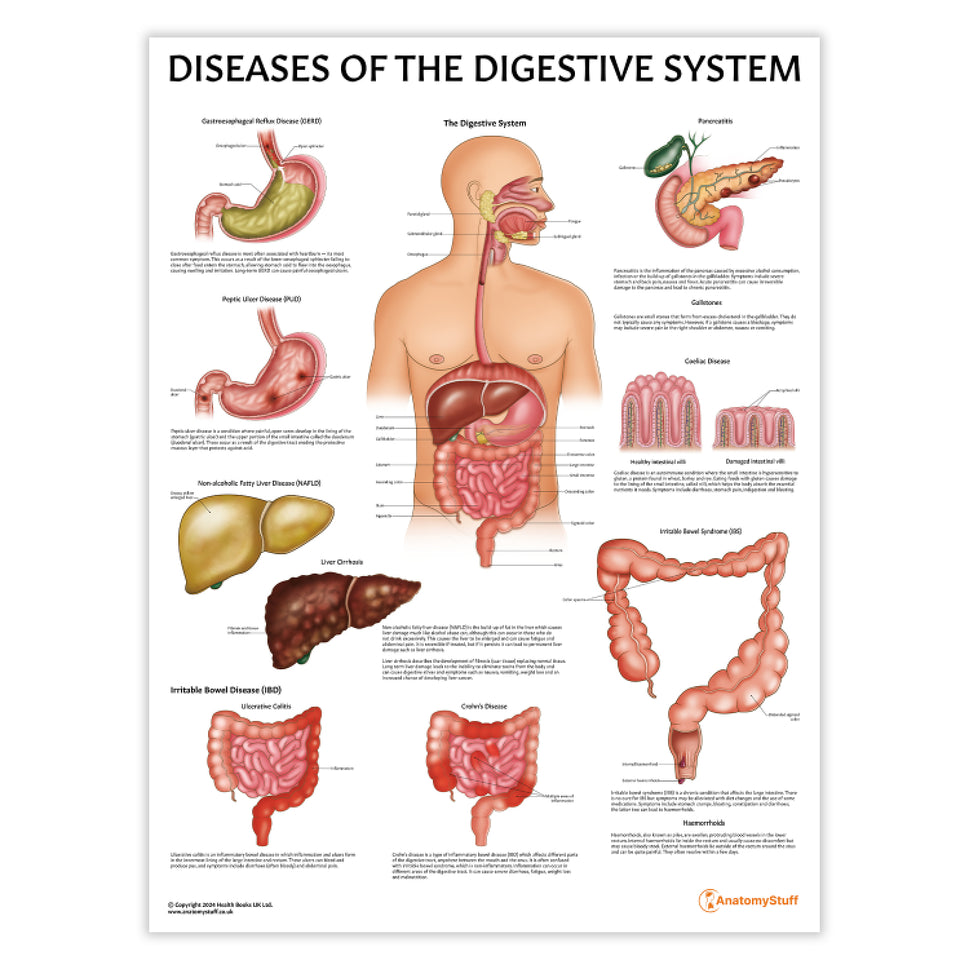

Enhance medical education with our collection of digestive system anatomical models including the stomach, liver, gallbladder, pancreas & colon models. Discover the anatomy of healthy organs as well as common gastrointestinal diseases such as stomach ulcers, gallstones and liver cirrhosis. Our digestive system anatomy posters are ideal for study and patient education.

At AnatomyStuff we stock a diverse range of digestive system anatomical models to suit your training needs. From budget models and affordable medical education posters to highly advanced 3D printed bowel models, you can transform medical training and patient education. As well as our own exclusive collection, we are proud resellers of 3B Scientific, Anatomy Lab, Denoyer-Geppert Science Company, ESP Models, Erler Zimmer and GPI Anatomicals. Explore our exclusive collection of digestive system anatomy charts, posters, fine art prints and digital anatomy study guides. Discover the anatomy of key organs like the liver, stomach, pancreas and bowel as well as the pathophysiology of common conditions like peptic ulcer disease, coeliac disease, IBD and much more. We have anatomy posters suitable for school children all the way up to medical degree level. From a liver anatomy poster to a digital study guide all about common GI disorders, find exactly what you need right here to enhance medical training and patient education.